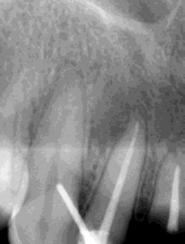

Las Figuras 1-3 muestran las imágenes de la cavidad bucal de la paciente. Se puede observar el deterioro generalizado de la salud bucodental, destacando la higiene dental deficiente, gingivitis, restauraciones dentales desajustadas, exposiciones radiculares, anodoncias parciales y caries radiogénica.

Las Figuras 4-13 son imágenes radiográficas de los dientes de la paciente que presen tan múltiples lesiones periapicales como consecuencia de las necrosis pulpares originadas por la radioterapia. Se realizaron los

tratamientos y retratamientos endodónticos necesarios para preservar los dientes en boca, evitando las exodoncias y por lo tanto minimizando el riesgo de generar osteorradionecrosis.